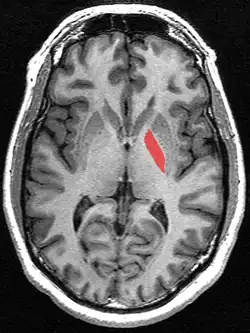

![]() Globus pallidus (in red) shown within the brain | |

The globus pallidus (GP), also known as paleostriatum or dorsal pallidum,[1] is a major component of the subcortical basal ganglia in the brain. It consists of two adjacent segments, one external (or lateral), known in rodents simply as the globus pallidus, and one internal (or medial). It is part of the telencephalon, but retains close functional ties with the subthalamus in the diencephalon – both of which are part of the extrapyramidal motor system.[2]

The globus pallidus is a structure in the brain involved in the regulation of voluntary movement.[8] It is part of the basal ganglia, which, among many other functions, regulate movements that occur on the subconscious level.